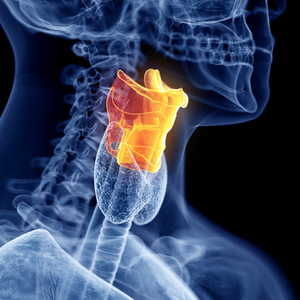

Balsenes karcinoma - balsenes vēzis